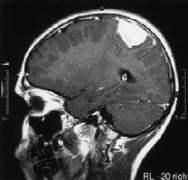

老人突然不爱说话,竟是因为较大脑膜瘤

69岁的张师傅突然变得一言不发,而且连走路也变得困难。这些怪异的举动引起了家人的警惕,家人以为是得了阿尔兹海默症,随后,张师傅被家人带到当地医院就诊。通过核磁共振在...